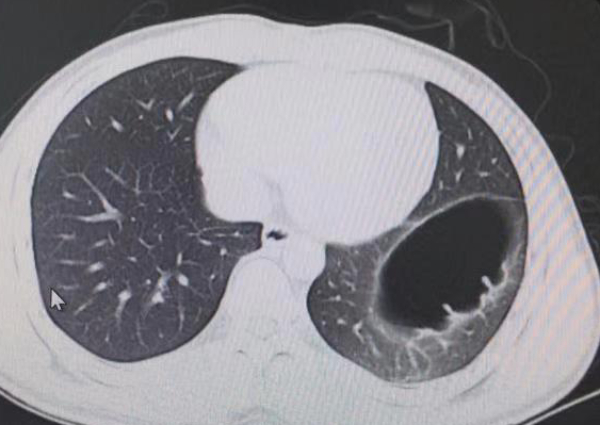

Trước sự ngạc nhiên của anh, bác sĩ nhanh chóng chẩn đoán và phát hiện ra anh bị thoát vị cơ hoành bẩm sinh. Điều này xảy ra khi cơ hoành ngăn cách ngực với bụng, có một lỗ mở cho phép các cơ quan bụng di chuyển lên trên ngực.

Ảnh chụp cắt lớp vi tính cho thấy thoát vị cơ hoành của Mai.

Trong trường hợp của Mai thì anh bị bẩm sinh, khiếm khuyết này đã có từ lúc sinh ra.

Bác sĩ Feng Jinhang đã quan sát và nghe thấy âm thanh kỳ lạ trong ruột của anh, điều này đúng như phỏng đoán ruột đã di chuyển lên ngực. Anh cần phải thực hiện một cuộc phẫu thuật để di chuyển các cơ quan nội tạng về đúng vị trí và sửa chữa lại cơ hoành.